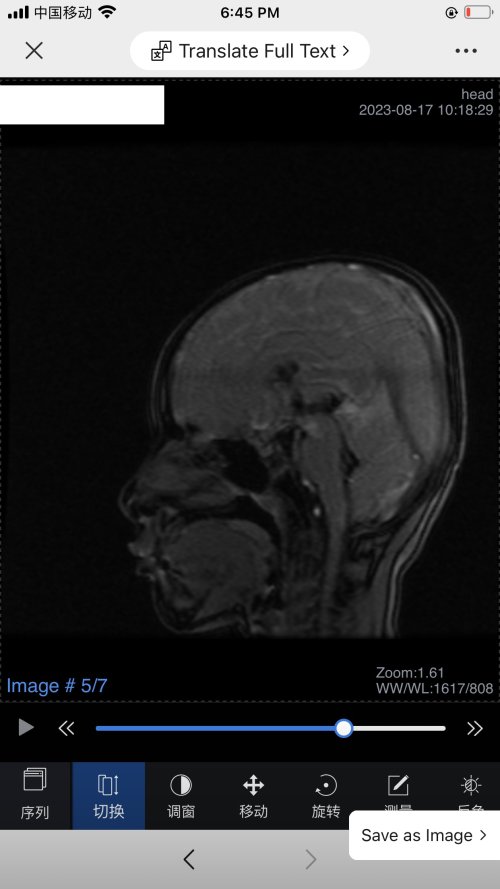

反馈下情况,孩子在国内的医院已经进行过一轮全面检测,没发现什么问题,但是现象是存在的。医生也没什么办法。医生说核磁共振和脑电图没问题,我们也不是很看得懂,各位如果懂的,请指点一下。另外进行了部分基因检测,没发现异常。下一步,我们国庆后打算去更权威的医院去碰碰运气。谢谢各位!

513.6 KB 查看: 103

532.8 KB 查看: 142

551 KB 查看: 132

526.8 KB 查看: 133

510 KB 查看: 103

506.4 KB 查看: 124

495.7 KB 查看: 165